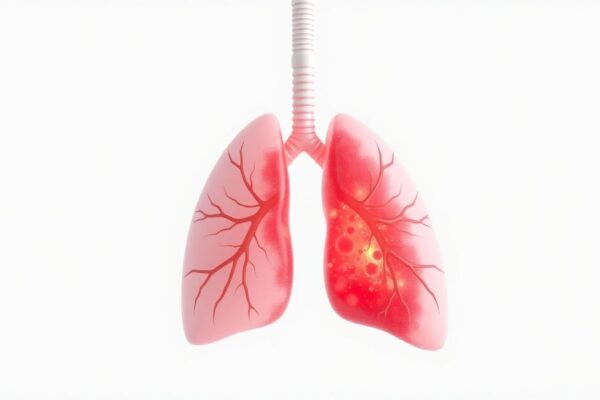

Vaping and Lung Damage: What the Science Really Says (2026 Update)

Vaping has been marketed as a “safer alternative” to smoking, but emerging research reveals a disturbing truth: e-cigarettes pose significant, unique risks to lung health. As of 2026, the scientific consensus is clear– vaping causes measurable damage to respiratory systems, particularly among young users. This comprehensive update examines the latest research on how vaping affects…